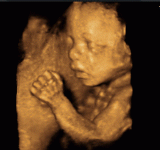

ambulante Operationen, 3D/ 4D Ultraschall ( z.B. in der Schwangerschaft "Babyfernsehen"), hochauflösender Brustultraschall, Farbdoppleruntersuchungen, Hebammenbetreuung, Krebsvorsorge, Ernährungsberatung, Impfungen, Infusionen, Laboruntersuchungen, Blutuntersuchungen, Ersttrimesterscreening (Nackentransparenzmessung in der Frühschwangerschaft)

- 3D und hochauflösenden 4D Utraschall (bereits in der Frühschwangerschaft)